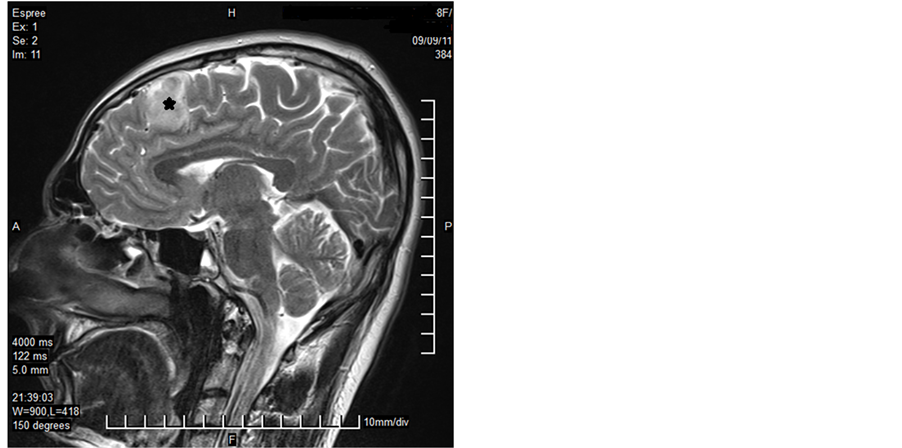

A 32-year-old male patient presented with a generalized epileptic seizure. Neurological examination was normal. Cerebral computerized tomography (CT) and magnetic resonance imaging (MRI) revealed a small solid lesion localized at the frontal lobe, without clear dural attachment, inhomogeneously hyperdense/hyperintense, with irregular enhancement after contrast injection (Figure 1). The patient underwent operation with a preoperative diagnosis of high grade glioma. Histopathologically a dense hypercellular glial tumor was observed. Histopathological and immunohistochemical features (Figure 2 and Figure 3) are summarized in Table 1. A diagnosis of APXA was given. Six months later control MRI revealed a recurrent mass lesion. The morphologic features of the recurrent tumor were similar with that of the primary tumor except for that necrosis was present in the recurrent tumor. Histopathological and immunohistochemical features (Figure 4) are summarized in Table 2. Recurrent tumor was also diagnosed as APXA. In both tumors BRAF V600E mutation was detected by FISH method. p16 mutation was not observed.

Figure 1. MRI revealed a small solid lesion at the frontal lobe, without clear dural attachment (Case 1―primary tumor; asterix).